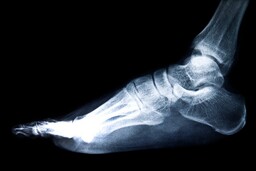

Luustomme

Ihmisessä on yli 200 luuta. Pisimmät luut ovat jaloissa, pienimmät korvan sisällä.Päätä suojaavat pääkallon luut, jotka liittyvät ihmisen kasvuvaiheen jälkeen kiinni toisiinsa.

Lantioluut muodostavat maljakon, jossa suolisto on hyvässä suojassa. Jalkojen isojen luiden nimet ovat reisiluu ja sääriluu. Niiden välissä on polvilumpio, jota voit sormillasi varovasti liikuttaa, kun pidät jalkaasi rentona.

Kuvia luista